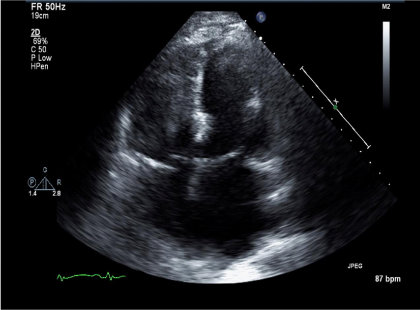

Vital signs on presentation at the outside hospital were: Temperature 38.1 F, Heart Rate of 90-101 beats/minute, Respiratory Rate 20-40 breaths/ minute, mean arterial pressure of 70 mmHg and oxygen saturation of 94% on VentiMask 40%. On examination at our hospital he was found to be tachypneic at 33 breaths/minute requiring Bi-level positive airway pressure (BiPAP), heart rate-106 beats/minute, mean arterial pressure-64 mmHg and oxygen saturation of 90% on VentiMask 40%. He appeared confused and lethargic. Neck exam was positive for jugular venous distension. He had decreased breath sounds bilaterally and the LVAD hum was heard on cardiac exam. On neurologic exam, he did not follow any commands, was aphasic with a right facial droop and had right hemiplegia. On checking with the outside hospital, due to his acute distress and lethargy, a neurologic exam was not performed. Laboratory tests on admission were consistent with hemolysis and acute renal failure (Table 2). LDH was elevated at 3012 (IU/L) up from<500 a week ago. Chest radiography was consistent with pulmonary edema (Figure 1). CT Head revealed a left non-hemorrhagic MCA infarct with mild mass effect and mild midline shift from left to right (Figure 2). Urine in his Foley bag was orange- red in color. A stat echocardiogram (Figure 3) obtained revealed a dilated left and right ventricle and an aortic valve opening every beat that was opening every other beat on his last clinic visit, 3 weeks ago. This further confirmed the working diagnosis of an acute LVAD thrombus complicated by an embolic event leading to the acute ischemic infarct. An emergent Neurology consultation was obtained and after reviewing his physical exam and CT-brain with the Neurology team, the diagnosis of acute ischemic stroke with significant right hemiplegia was confirmed. Since he was outside the recommended treatment window for thrombolytic administration for his acute stroke (9hours against the recommended, the Neurology team recommended against the use of systemic thrombolysis due to the increased risk for bleeding vs. reducing infarct size.

Figure 3 Echo- at Presentation. Apical-4 chamber view showing a dilated left and right ventricle despite increasing the lvad rpm.